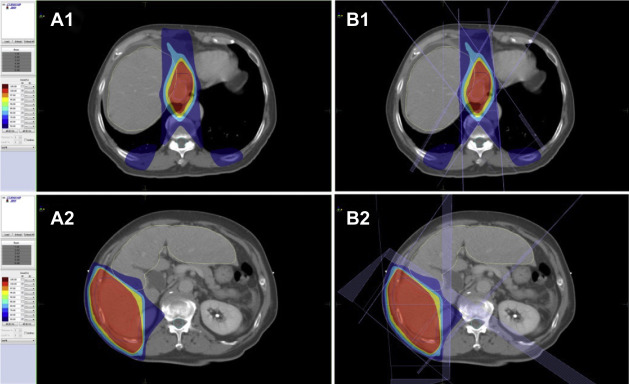

Effect of treatment with sorafenib and radiotherapy evaluated by abdominal ...

Figure 3.

Effect of treatment with sorafenib and radiotherapy evaluated by abdominal magnetic resonance imaging. (A), (B) Pretreatment and post-treatment in arterial phase. Part (B) also shows decreased tumor size in arterial phase after treatment (arrow); (C), (D) pretreatment and post-treatment in delayed phase. Part (D) also shows decreased tumor thrombus in the portal vein after treatment (arrowhead).

Figure 4.

Effect of treatment with sorafenib and radiotherapy evaluated by abdominal magnetic resonance imaging. (A) Tumor thrombus in the inferior vena cava before treatment in delayed phase; (B) decreased tumor thrombus in the inferior vena cava after treatment (arrow); (C) tumor thrombus in the portal vein before treatment in coronal view; and (D) decreased tumor thrombus in the portal vein after treatment (arrow).